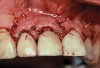

Implant mobility is not a useful diagnostic parameter. If an implant is mobile, it should be considered failed and removed. Conversely, implants may have advanced peri-implantitis with bone loss from 50% to 90% of implant length and still exhibit no mobility when examined clinically (Figure 1).

Figure 1  An implant, 12 mm in length, with advanced peri-implantitis and 10-mm bone loss, exhibiting no mobility.

Figure 1